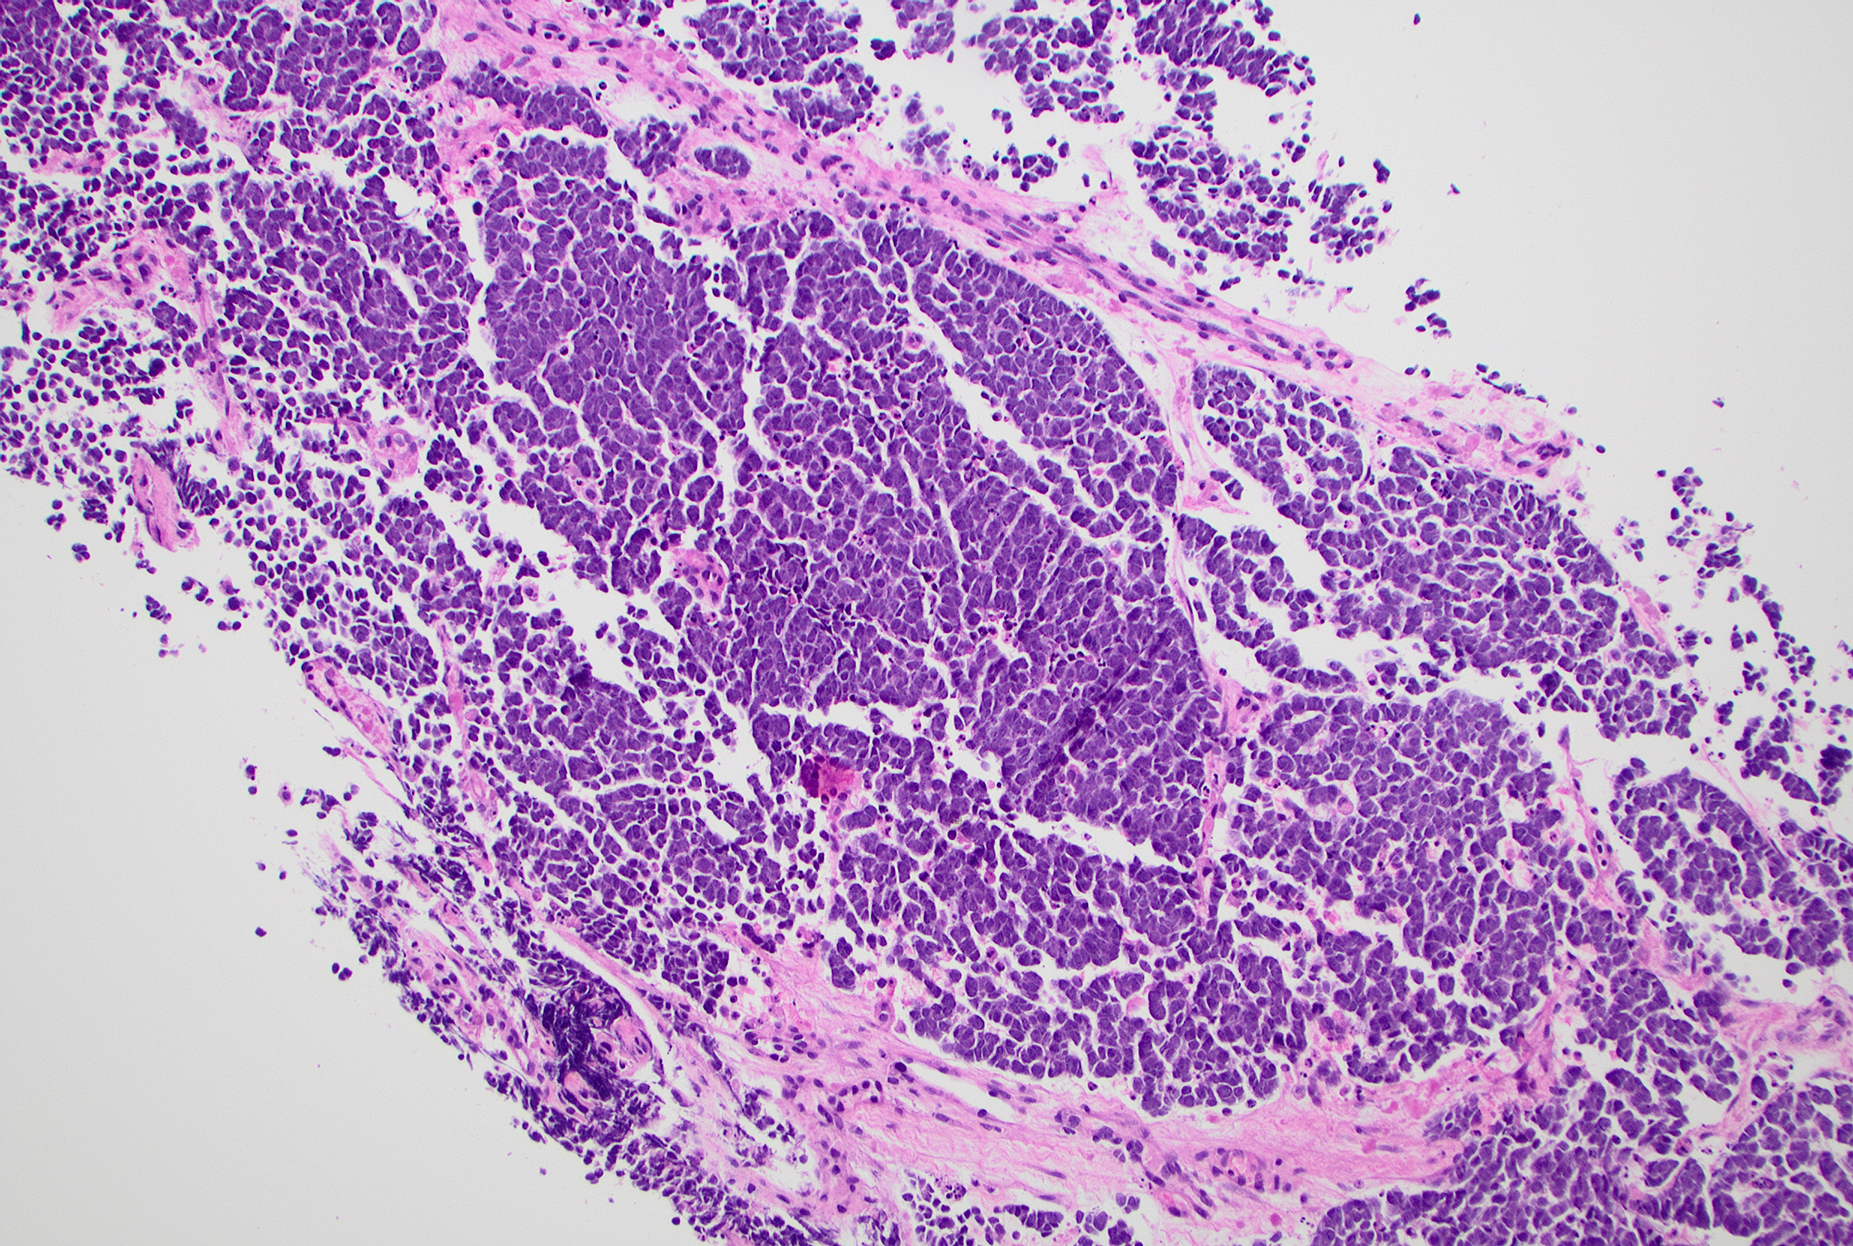

• Figure 3: Core biopsy of forearm mass, H&E stain, 100x

The touch preparation and biopsy slides (Figures 1–3) show a small blue cell neoplasm composed of loosely cohesive and dispersed neoplastic cells with high nuclear-to-cytoplasmic ratios and fine, stippled chromatin. Nuclear molding is present. Immunohistochemical stains on the biopsy specimen reveal that these neoplastic cells are positive for CK20 (Figure 4, paranuclear dot-like pattern), CAM5.2, INSM1 (Figure 5), synaptophysin, chromogranin, and MCPyV (Figure 6), while negative for CD45, S100, TdT, CD34, desmin, p63, and CD99. The overall cytomorphological findings, along with the immunoprofile, are consistent with Merkel cell carcinoma (MCC). MCC is a fast-growing dermal tumor characterized by neuroendocrine cytology and an immunophenotype of neuroendocrine differentiation. The tumor predominantly affects elderly White individuals and those who are immunosuppressed.

MCC is a highly aggressive primary cutaneous neuroendocrine malignancy with an expansile, nodular, or infiltrative growth pattern. Architecturally, these tumors are characterized by sheets, nests, or occasional trabecular arrangements of monomorphic cells.

The cytologic features include a spectrum of small to intermediate and large cells. The neoplastic cells display high nuclear-to-cytoplasmic ratios and "salt-and-pepper" (fine stippled) chromatin with numerous mitotic figures and apoptotic bodies.  Diagnostic confirmation relies on a specific immunohistochemical profile, most reliably indicated by a characteristic perinuclear dot-like staining for CK20 (positive in ~95% of cases) or neurofilament, alongside positivity for neuroendocrine markers such as INSM1, synaptophysin and chromogranin.